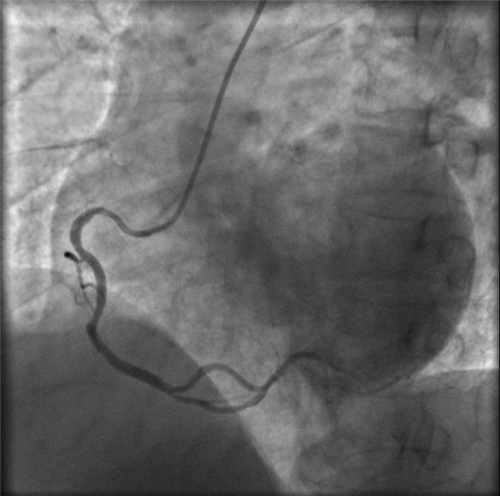

右冠近段嚴重狹窄,未見右向左的側枝循環(huán)

再行右冠造影,右冠近段也嚴重狹窄,未見右冠向左冠的側枝循環(huán)。